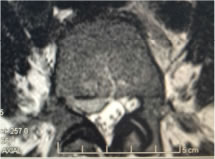

Une compression radiculaire peut être dûe à une hernie discale comprimant la racine ou à une sténose foraminale ce qui engendre les symptômes classiques d’une « sciatique ».

Parfois l’ensemble du canal lombaire est rétrécis ce qu’on appelle un « canal lombaire étroit » et ceci cause les symptômes typiques d’une « claudication neurogène » caractérisés par une douleur avec faiblesse ou lâchage des jambes lors de la marche.

Les troubles dégénératifs de la colonne cervicale peuvent entrainer une compression des nerfs cervicaux, les plus fréquement les racines C5, C6, et C7, ou une compression de la moelle épinière engendrant une « myélopathie cervicale ». Le but de la chirurgie cervicale est de soulager la compression nerveuse, des racines ou de la moelle épinière.